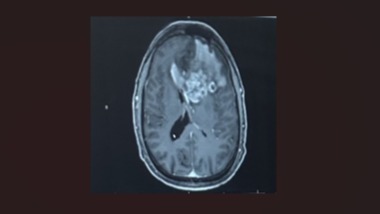

On Saturday, February 28th, our dad, Trevis Bassett, was taken to Jersey Shore Hospital with stroke-like symptoms. The hospital did a CAT scan and discovered a large left frontal lobe mass. He was then taken by ambulance to Geisinger in Danville. Geisinger did an MRI and found a large left frontal lobe tumor that extends over to the right frontal lobe. The doctors diagnosed the 3.9 by 4.8 by 4.4cm tumor as stage 4 glioblastoma, a highly aggressive brain cancer. Glioblastoma is always stage 4 and is diagnosed in 14,500 Americans a year. More than 10,000 Americans die from this every year, meaning 1 out of 3 survive. The average survival rate is 12-15 months with surgery and treatment. On March 3rd, he had a 5-hour long surgery to remove as much of the mass as they could. He came home March 5th, to heal, before starting chemotherapy and radiation. Unfortunately, our father will be unable to work during this time. He runs his own business, alongside our mom, who is taking care of him during this time. Anyone who knows our dad knows he's a hardworking family man. He goes above and beyond for his children, his grandkids, his wife, and his clients. We are reaching out to our community for help. If you are able or unable to donate, please consider sharing this post. Our family appreciates every donation, share, thoughts, and prayers that you give. We want our dad to be that 1 out of 3. Please help us help him fight for his life.